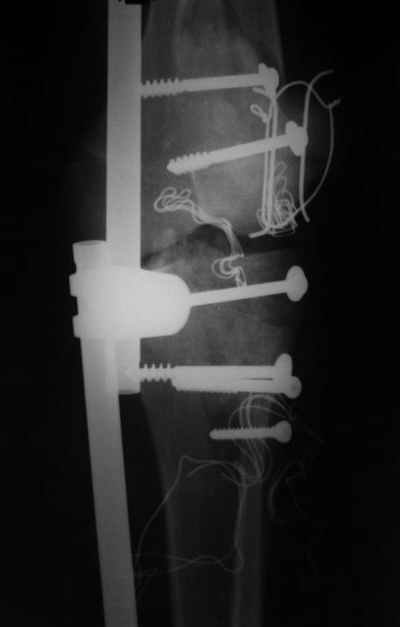

ET> обработку и внешнюю фиксацию, картинки в приложении.

Evgueny Tschekashkin 14 Декабрь 2004, 18:41

Вид раны на сегодня...

4 cутки после травмы.